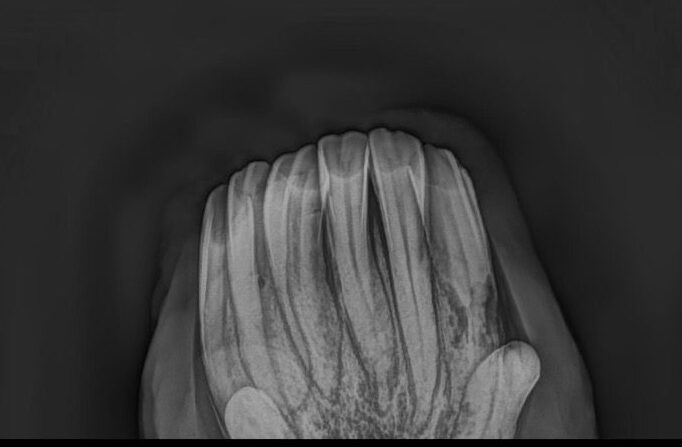

- röntgenologische Untersuchung zur Bestätigung der Verdachtsdiagnose EOTRH

- deutliche Befunde erkennbar

- resorptive und hyperzementotische Veränderungen an den Schneidezähnen/Schneidezahnwurzeln